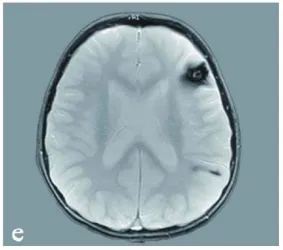

此外,还包括一个位于左额叶的致痫病灶(图1,e)。

图e:显示患儿幕上其他海绵状血管瘤(左额叶及顶叶)。